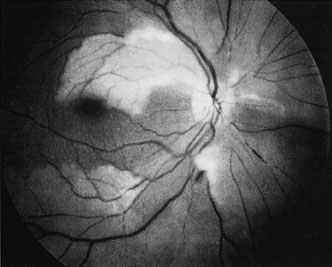

Ophthalmic artery obstruction is characterized by an initial opacification of the entire retina in a manner similar to that of central retinal artery obstruction (Fig. 4A). The cherry-red spot may or may not be present, however.119 The difference between an ophthalmic artery obstruction and central retinal artery obstruction is that in an ophthalmic artery obstruction, with time, optic atrophy develops, as does varying amounts of pigmentation due to the lack of perfusion of the retinal pigment epithelium (see Fig. 4D). This pigment is generally diffusely scattered throughout the posterior pole but it may also be seen in greater amounts in the periphery.

Fig. 4. A: Ophthalmic artery obstruction showing a cherry-red spot: the visual acuity was no light perception. B: At 26.2 seconds, the retinal vessels are filled, but no dye is seen in the choroidal circulation. C: By 37.7 seconds, the choroidal circulation is more visible, and a doughnut-shaped area of hypofluorescence is noted. D: Six months after the initial photographs, optic atrophy is present, as is atrophy of the retinal vessels. Diffuse pigment disturbance is evident.

Intravenous fluorescein angiography generally shows moderate to marked abnormalities in the filling of the choroid, in addition to a delay in filling or even nonfilling of retinal vessels (see Fig. 4B and 4C). Staining of the retinal pigment epithelium can also be seen; this staining either can occur locally in the macular area or it can be diffuse.119 The electroretinogram shows abnormalities of both a- and b-waves, reflecting ischemia to both the inner and outer retina. Almost all reported patients have had an initial visual acuity of no light perception; virtually no patients can be expected to have a final visual acuity better than that.119 An acuity of no light perception is a clue to the presence of an ophthalmic artery obstruction. Because relatively few patients with central retinal artery obstruction have an initial visual acuity of no light perception, no light perception usually suggests the likelihood of some obstruction of the choroidal circulation.14